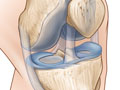

- Find problems in the knee joint, such as arthritis, bone tumors, or infection, or damaged cartilage, meniscus, ligaments, or tendons.

- The ligaments, meniscus, tendons, bones, and joints look normal in size, shape, and location.

- No growths, such as tumors, are present.

- No broken bones (fractures), extra fluid, or loose bodies are present.

- No signs of inflammation or infection in bones, joints, or soft tissues are present.

- Bones show an injury or a fracture. The MRI also may show a collection of fluid, which could mean an infection is present.

- Ligament or meniscus tears are present.

- Tendon tears are present. The MRI may also show a thickening, meaning surgery or a tear you had in the past or repeated stress.

- Growths, such as tumors, are present.

- Changes common to arthritis are present.